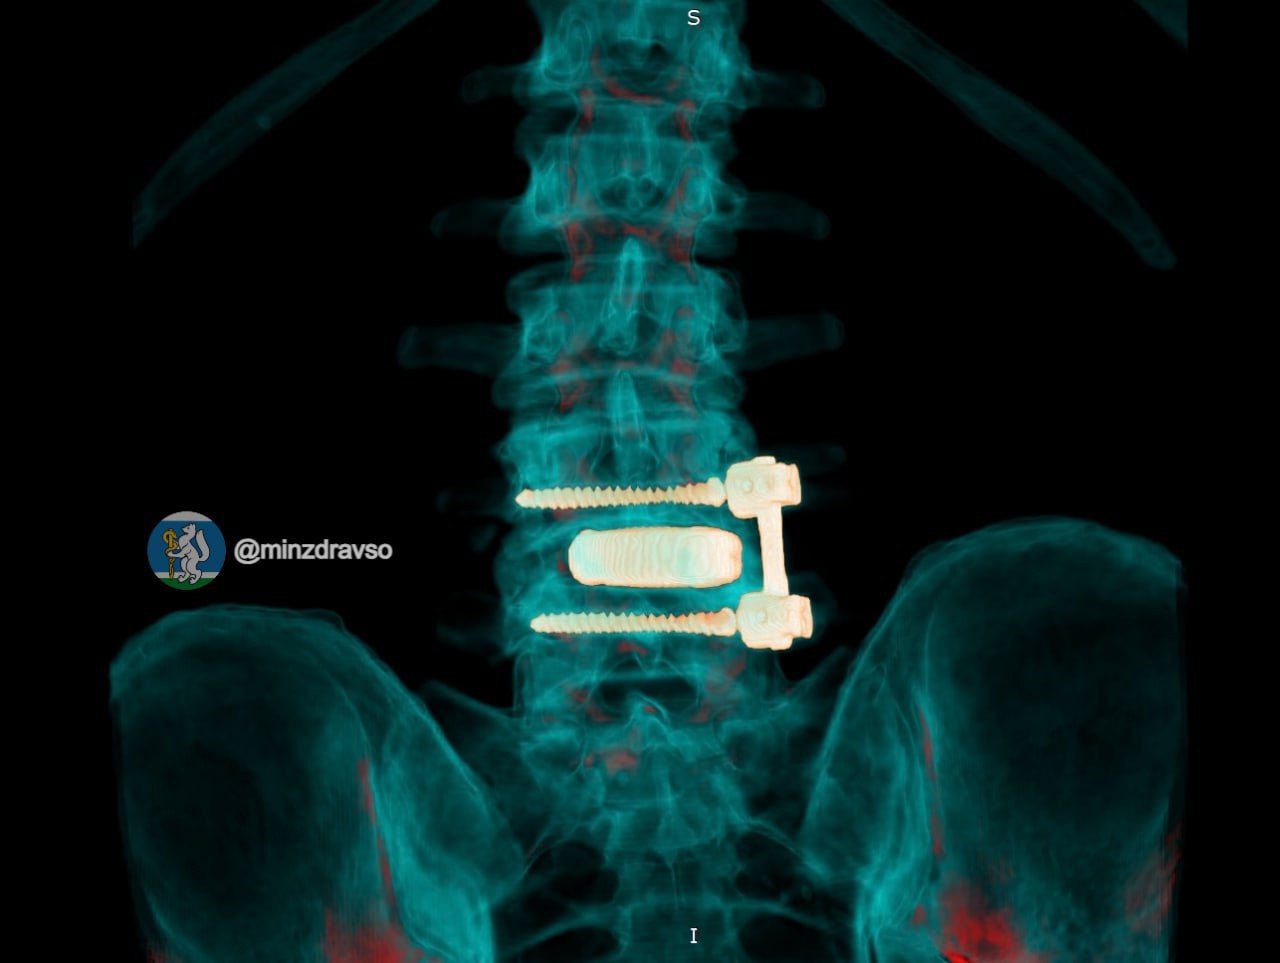

Лечить мужчину стали в госпитале для ветеранов войн, где ему сначала удалили инфицированную конструкцию и провели санацию очага воспаления, а затем после курса антибактериальной терапии восстановили опороспособность позвоночника с помощью титанового 3D-импланта, изготовленного по индивидуальным параметрам.

Фото: Минздрав Свердловской области

«Фиксацию выполнили российскими спонгиозными винтами. Уже в первые сутки после операции болевой синдром полностью купировался, пациент самостоятельно встал и начал ходить»,

– рассказали в Минздраве.